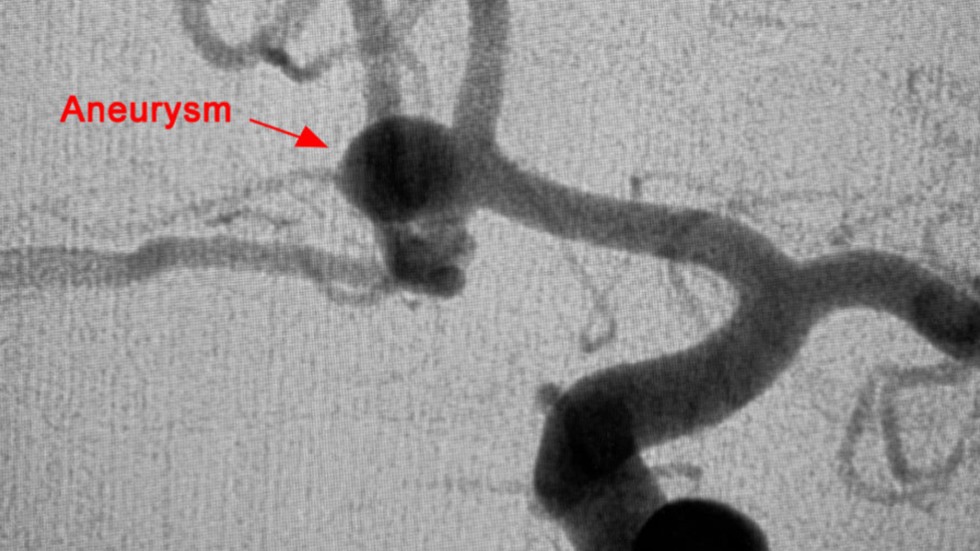

Surgical Clipping

1 of 3

Surgical clipping, also called open microsurgery or craniotomy, is an open surgery performed through a surgical opening in the skull. Using an operating microscope and tiny instruments, the surgeon attaches a small metal clip at the base of the aneurysm. Because blood is prevented from flowing into the aneurysm, the chances of it rupturing are greatly reduced. Recovery time is typically four to six weeks. Pictured: Before Surgical Clipping